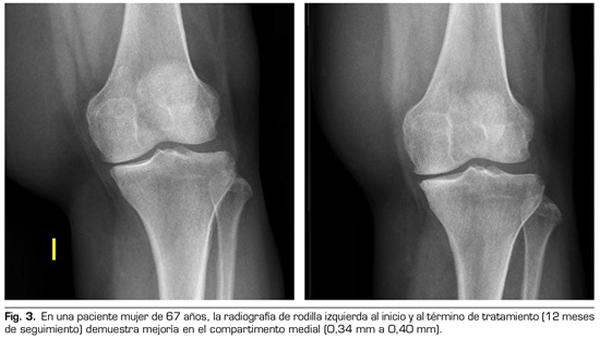

Con respecto a las variables radiológicas, al valorar a 53 de los 115 pacientes que cumplieron un año de seguimiento después del tratamiento con ozono, se observó que el compartimento interno aumento significativamente de 4,12 ± 1,41 mm a 4,4 ± 1,35 mm (p = 0,0008) y el compartimento externo aumentó de 6 ± 1,37 a 6,16 ± 1,4 mm (p = 0,0753) (Tabla II). Se presentan 2 casos clínicos como muestra del cambio radiológico en los compartimentos interno y externo (Figuras 2 y 3).

Para la evaluación radiográfica de la articulación tibiofemoral medial y lateral, se realizaron radiografías bilaterales anteroposteriores, con ambas piernas apoyadas y completamente extendidas, en carga según protocolo estandarizado (9). Todas las imágenes radiográficas se adquirieron digitalmente mediante un sistema de comunicación de archivo de imágenes (PACS). Se evaluó a 53 pacientes de los 115 que cumplieron un año de seguimiento tras la primera infiltración. Se midió la distancia femorotibial en la radiografía en los compartimentos medial y lateral en la distancia percibida como la más estrecha del espacio articular, y utilizando el programa de medición PACS. Todas las evaluaciones fueron llevadas a cabo por un solo autor, con el fin de reducir la variación interobservador, cuyo coeficiente de variación para medidas repetidas es 3-8 % (9,10).